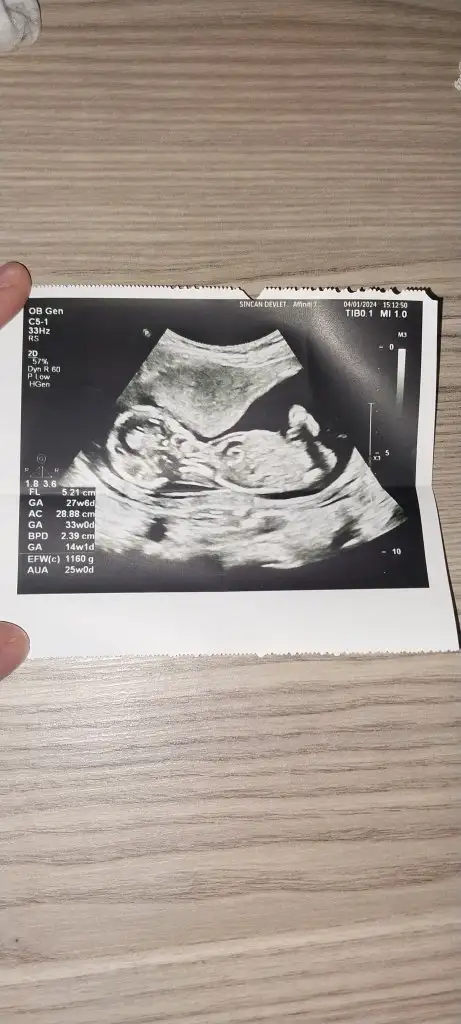

Plesanta sağ da erkek canımmerhabalar ilk bebişimiz merakla bekliyoruz6. haftanın içindeyken gitmiştik,karından ultrason tahmininizi çok merak ediyorum

Eki Görüntüle 3398806

teşekkür ederim inşallah sağlıkla rabbim kucaklamayı nasip etsin önceden bir düşüğüm var hep dua ediyorumPlesanta sağ da erkek canım